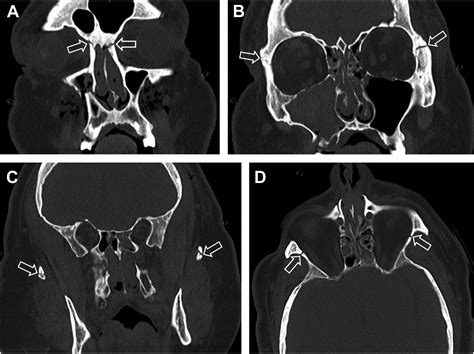

The classification system developed by René Le Fort remains the gold standard for describing patterns of maxillary fractures. While a Lefort I fracture affects the lower maxilla and a Lefort II involves the mid-maxilla and nose, the Lefort III fracture is defined by a transverse fracture line that traverses the frontozygomatic suture, the orbit, and the nasofrontal suture. Essentially, the entire facial skeleton is disconnected from the skull, creating a "floating" midface.

Due to the complexity of these injuries, patients often present with a characteristic "dish-face" deformity, where the middle of the face appears sunken or pushed backward. The diagnostic process is rigorous, often requiring high-resolution CT scans to map the displacement of bone fragments precisely before surgical planning can begin.